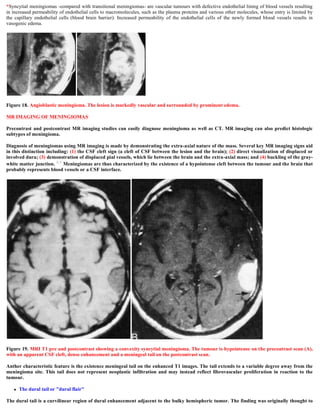

Figure 18. Angioblastic meningioma. The lesion is markedly vascular and surrounded by prominent edema.

*Syncytial meningiomas -compared with transitional meningiomas- are vascular tumours with defective endothelial lining of blood vessels resulting

in increased permeability of endothelial cells to macromolecules, such as the plasma proteins and various other molecules, whose entry is limited by

the capillary endothelial cells (blood brain barrier). Increased permeability of the endothelial cells of the newly formed blood vessels results in

vasogenic edema.